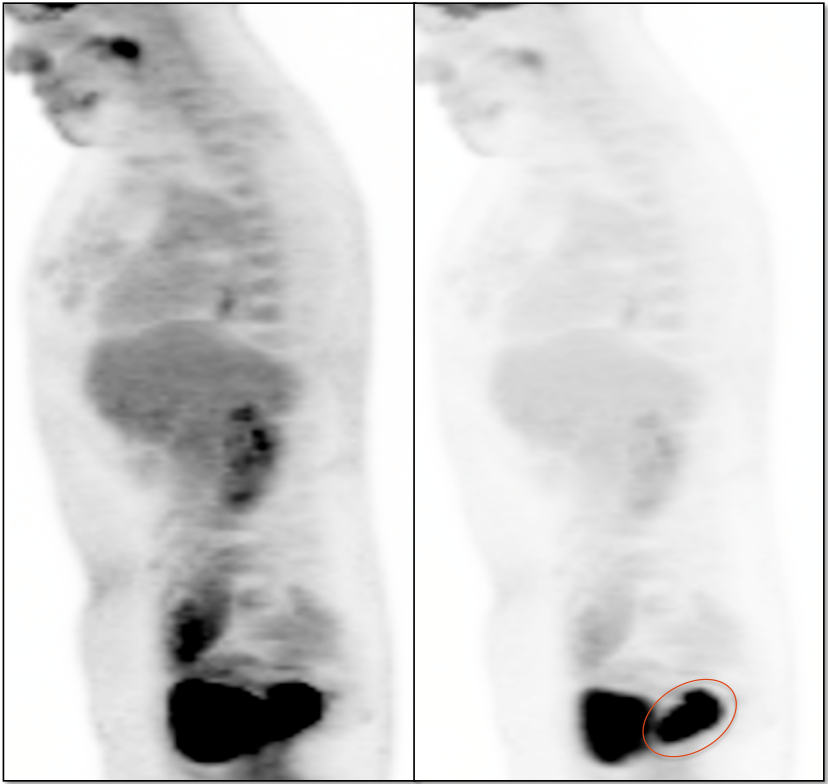

Recurrence, Restaging & Surveillance:

• PET/CT is utilized for patients with known or suspected recurrent disease (or at high risk for recurrence).

• Distinguishing recurrence from post-therapeutic inflammation.

Metastatic Disease:

• Lymphatic spread to pelvic and retroperitoneal lymph nodes.

• Hematogenous spread, often to lungs, liver, and bone.